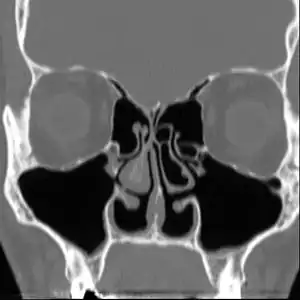

Empty nose syndrome (ENS) is a clinical syndrome, the hallmark symptom of which is a sensation of suffocation despite a clear airway. This syndrome is often referred to as a form of secondary atrophic rhinitis. ENS is a potential complication of nasal turbinate surgery or injury.[1][2] Patients have usually undergone a turbinectomy (removal or reduction of structures inside the nose called turbinates) or other surgical procedures that injure the nasal turbinates.

| Altered nasal anatomy after bilateral subtotal inferior turbinectomy, the removal of most turbinate tissue. | |